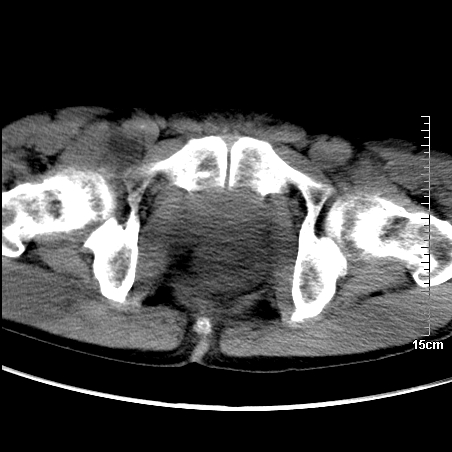

1、骶尾部巨大软组织肿块,部分骶尾骨以被软组织肿块代替,呈不规则侵蚀;病变突向盆腔内;增强扫描病变呈不均质强化;首先考虑脊索瘤。不支持的一点就是病变内无钙化。

2、发生于骶尾椎者须与骨巨细胞瘤鉴别,骨巨细胞瘤一般发在上疗骶椎,肿瘤内无钙化,一般无侵袭性生长的表现。

部分骶尾骨已被软组织密度的肿瘤所取代,同意“首先考虑脊索瘤,不除外转移瘤”的意见。